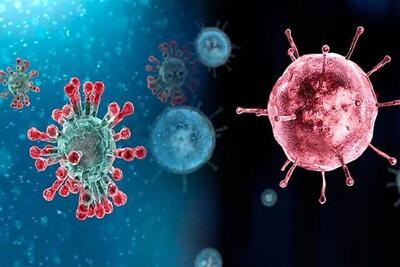

سازمان سیا ارزیابی خود درباره منشا بیماری کووید-۱۹ را تغییر داد

سازمان اطلاعات مرکزی آمریکا (سیا) با تغییر رویکرد قبلی اش که منشا بیماری کووید-۱۹ را انتقال طبیعی این ویروس می دانست، در ارزیابی جدید خود اعلام کرد که این ویروس احتمالا از یک آزمایشگاه در چین شیوع یافته بود.